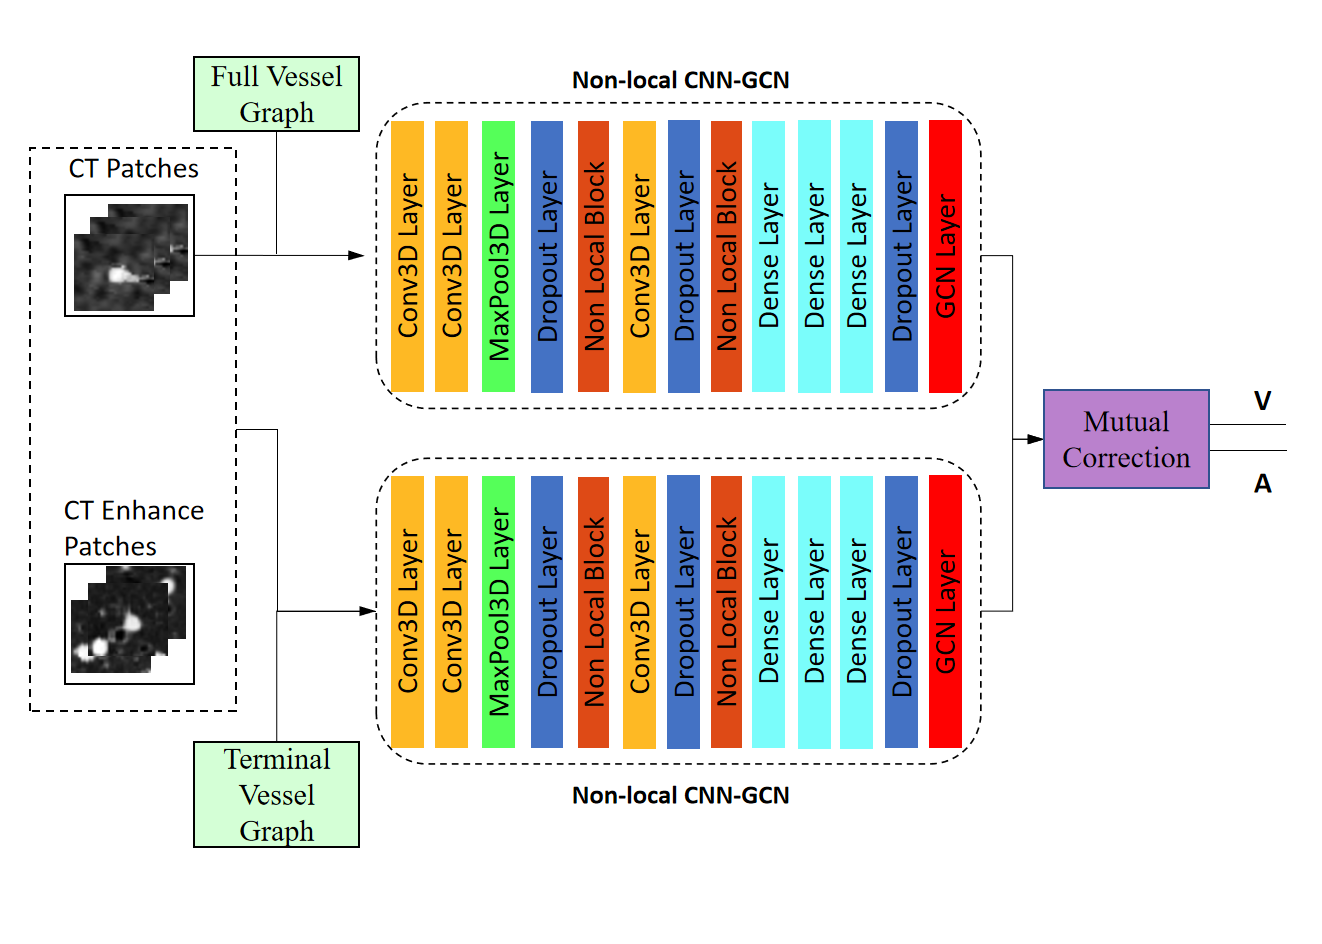

Traditional CNN network has limitation in capturing long range dependencies which extract the global understanding of visual scenes. In this paper, we consider both image information and connectivity information by connecting Non-local CNN and GCN. The Non-local CNN considers the global context information of the image, while the GCN module can learn the local and graph connection information. Combining these two modules together is useful for analyzing the vascular tree. In order to connect the Non-local CNN network with the GCN network, this paper adapt the end-to-end method of CNN connecting GCN proposed by Zhai et al.[13]. In the preliminary classification of A/V, the learning ability of the Non-local CNN-GCN method for the A/V features is better than that of the traditional CNN-GCN, Non-local CNN3D and CNN3D.

In this paper, for each point on the vascular topology tree, the orientation information of each node is used to extract the local patch of size S = [32, 32, 3] that should be perpendicular to the vascular direction from the CT image. A patch is labeled either artery or vein,i.e. {1, 2}, based on the label of the center voxel. We randomly select node b = 128 and their patches from our graph structure T as input, and we need the image patches of these neighbors n. Take NB of size b × n × s as the input to the Non-local CNN-GCN network, where n is the number of neighbors. Then the Non-local CNN-GCN classifier presented in this paper is trained and each center voxel is predicted to be an artery or vein. The Non-local CNN-GCN classifier adopted in this paper is shown in Fig. 8.

We propose that the Twin-Pipe network is expected to learn the difference of A/V characteristics caused by different levels and improve the accuracy of the preliminary classification. In this paper, a Twin-Pipe network is designed, in which one pipe network trains the full vessel graph to learn the image information and global connectivity, and the other pipe network specially trains the terminal vessel graph to learn the terminal structure characteristics. Finally, the preliminary classification results are obtained through the mutual correction module. The terminal vessel graph is the set of terminal branches in the full vessel graph, and the extraction process is shown in Fig. 9.

Aiming at the physiological feature of obvious accompanying artery at the end of trachea, for this purpose, the CT original image and vascular enhancement image serve as the input patch of another pipe of Twin-Pipe network, expecting to learn some additional distinguishing features of pulmonary arteries and veins. We perform vascular enhancement and normalization on the original image to enhance the differences between vessels and bronchi. Twin-Pipe network structure design in this paper is shown in the Fig. 10. Fig. 11 shows a case of extraction of terminal vessel particle and patch.